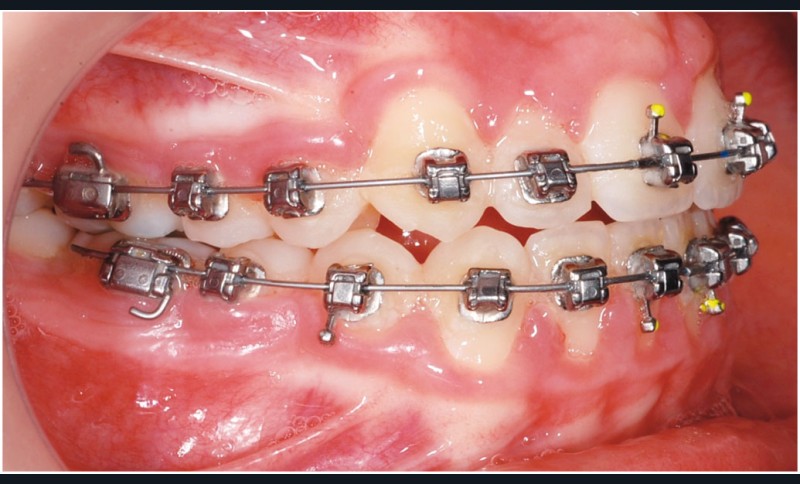

Le cas d’Anthony âgé de 11 ans et 7 mois qui présente une endomaxillie bilatérale associée à un léger encombrement mandibulaire dans un contexte de classe I squelettique hyperdivergente (fig. 1 à 10) est très représentatif de ce que peuvent apporter les forces légères appliquées aux alvéoles dentaires tout en intégrant des torques spécifiques qui permettent de contrôler parfaitement l’orientation radiculaire (fig. 11 à 29).

Le système laisse beaucoup de liberté dans l’interface entre bracket et arc : la vascularisation, et donc le recrutement cellulaire et la reconstruction osseuse s’en trouvent améliorés, la mise en place de l’occlusion se fait sous le contrôle de la matrice fonctionnelle, car les forces engagées restent en dessous de la puissance des forces masticatrices notamment.